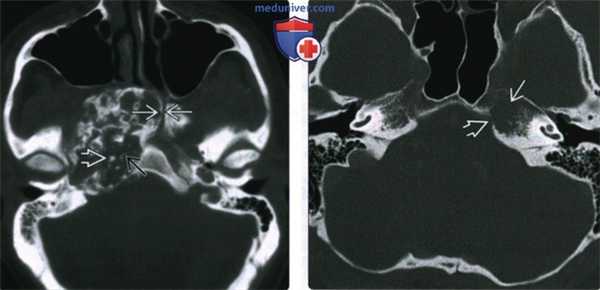

(Слева) При аксиальной КТ в костном окне в ткани крупной хондросаркомы определяются округлый и дугообразный очаги кальциноза. Центр опухоли лежит в каменисто-затылочной щели. Почти в 50% хондросарком выявляется кальциноз матрикса. Обратите внимание на небольшое сужение левого видиевого канала.

(Справа) При КТ в костном окне в аксиальной проекции у пациента с небольшой хондросаркомой верхушки пирамиды левой височной кости определяется плохо различимая деарукция кости с эрозией кортикального слоя. Обызвествленного матрикса не наблюдается. При МРТ определяется Т2-гиперинтенсивное контрастное объ емное образование той же локализации.